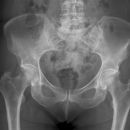

Hüftgelenk a.p.

Indikation

Cave: selten isoliert, meißt mit Luxation oder Azetabulum# kombiniert), Hüftgelenksluxation

Beurteilungskriterien

- CCD- Winkel (120-130°) Spongiosaarchitektur, Trajektorienverlauf im Schenkelhals (Cave: Bei nicht dislozierten SHF Diskontinuität der Trabekel oft einziges Frakturzeichen!)

- Shenton´sche Linie (Harmonischer Bogen aus kaudaler Schenkelhalskontur und der kranialen Zirkumferenz des For. obturatum)

- Gelenkstellung, Gelenkspaltweite (4-5mm nach medial, 3-4mm nach kranial), Luxation => Hüftkopf in ap und axialer Aufnahme in Azetabulum zentriert? Hüftkopfrundung?

- Azetabulumfraktur: vorderer und hinterer Pfannenrand, Pfannendachkontur, Köhlersche Tränenfigur, ggf. Zusatzaufnahmen (Ala- und Obturatoraufnahme), sowie CT

- medialer Azetabulumdachbogen (45° von der Hüftkopfmitte ausgehend nach vorne (!); Teil der lasttragenden Zone des Azetabulums, vgl. Obturatoraufnahme)

- Trochanter major et minor (Abriss, pertrochantäre #?)

- Weichteilzeichen (Fettstreifen medial des M.gluteus minimus zw. M.glutaeus minimus und medius, medial des M.iliopsoas; Konturschatten des M.obturatorius int.)